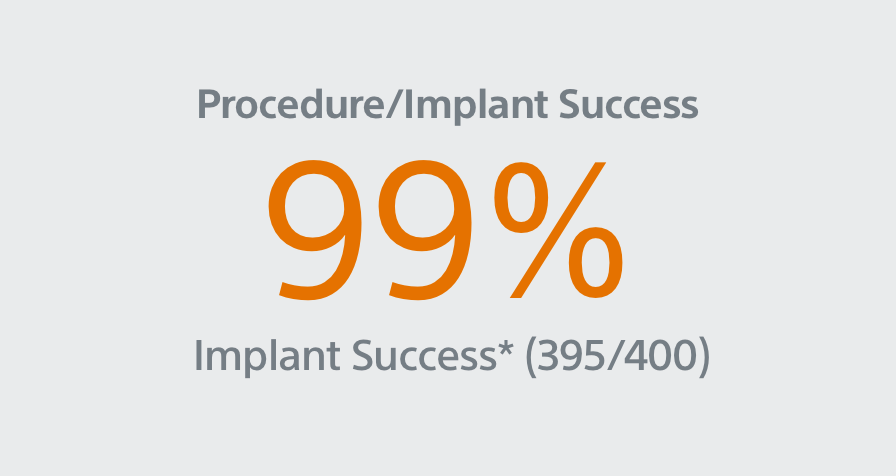

PINNACLE FLX

Study Design

- 400 patient, 29 US site, single arm, non-randomized trial evaluating WATCHMAN FLX for non-inferiority to safety and efficacy performance goals based on the WATCHMAN™ device.

Primary Efficacy Endpoints

The rate of effective LAA closure defined as any peri-device flow ≤5mm demonstrated by TEE at 12 months.